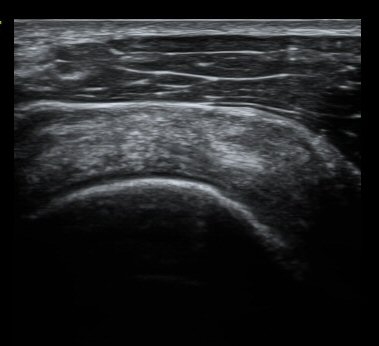

ȸÀü±Ù°³°£°Ý ³»Ãø Ⱦ´Ü¸é°Ë»ç¿¡¼­ °üÂûÇÑ °ß°©ÇÏ±Ù°Ç »óºÎ Á¾´Ü¸é°Ë»ç¿¡¼­ ¹Ì¼¼ÇÑ °£±ØÀÌ

°üÂûµÊ(±×¸² 3, 4). °ß°©ÇÏ±Ù°Ç È¾´Ü¸é°Ë»ç¿¡¼­µµ °ß°©Çϱٰdz» °£±ØÀÌ °üÂûµÊ(±×¸² 5).